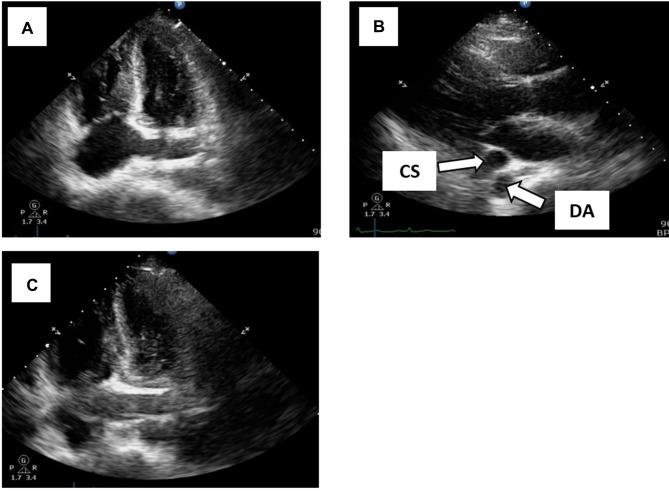

CASE PRESENTATION

Here we report a PLSVC case that was identified in chest radiography after the insertion of a CVC catheter in a patient with end-stage renal disease (ESRD). A 40-year-old woman with a history of type 2 diabetes mellitus, hypertension, dyslipidemia, and obesity was presented in the emergency room with dyspnea for 1 week. Acute hemodialysis was required because of the ESRD and pulmonary edema. The PLSVC condition accompanied by various complications that occurred in this patient became a dilemma for the nephrologist in determining the diagnosis and proper CVC management.

病例报告

在此,我们报告一例在终末期肾病(ESRD)患者置入CVC导管后经胸部X线检查发现的PLSVC病例。一名40岁女性,有2型糖尿病、高血压、血脂异常和肥胖病史,因呼吸困难1周就诊于急诊室。由于ESRD和肺水肿,需要进行急性血液透析。该患者出现的伴有各种并发症的PLSVC情况,给肾病科医生在诊断和恰当的CVC管理方面带来了难题。